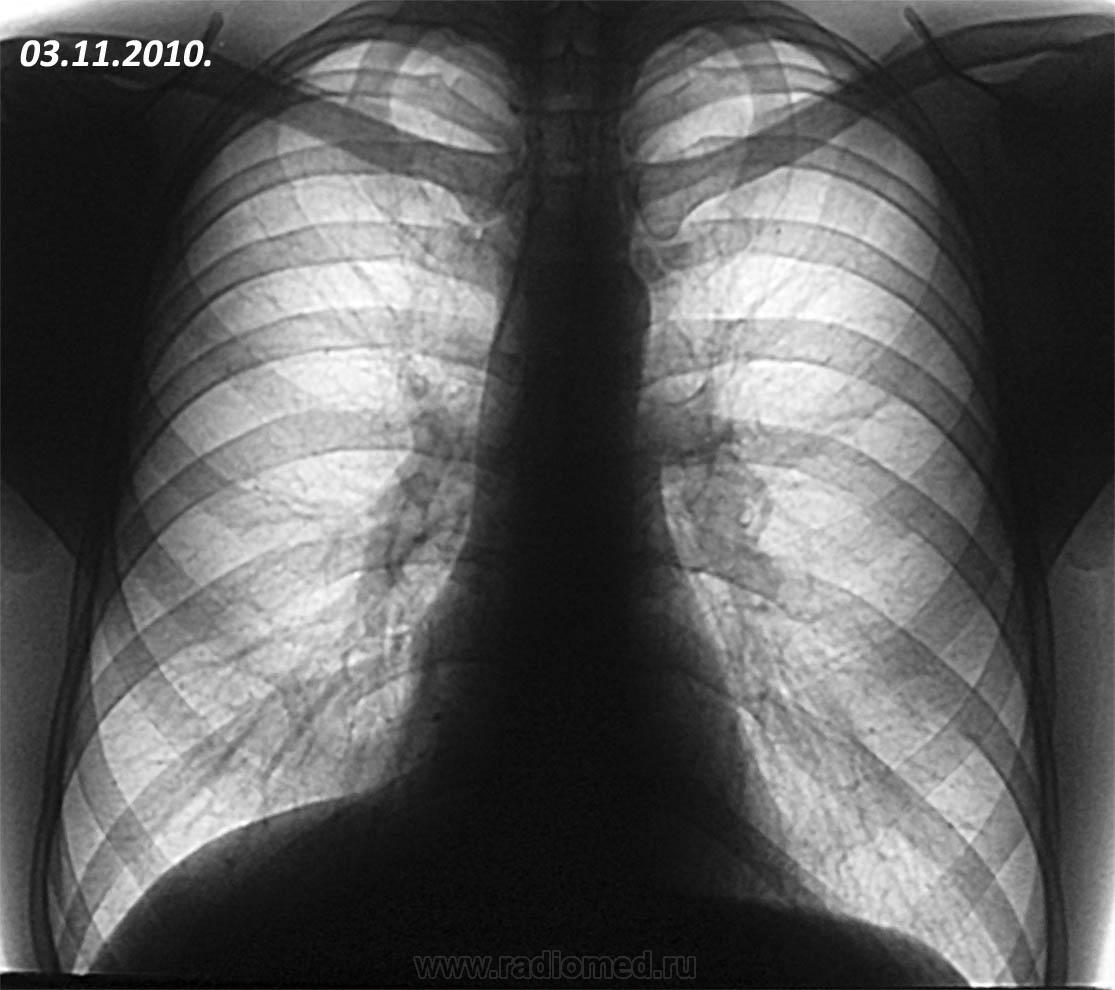

Пациент 1981 г.р., курильщик, жалобы на кашель с периодическими ухудшениями. Беспокоит около полугода. Поступил в пульмонологическое отделение госпиталя в июне 2010 года. Диагноз: плевропневмония. Позже госпитализировался неоднократно. Пневмония сопровождалась ретростарнальным плевритом с элементами организации. Полноценного регресса не было, исход в локальный пневмофиброз. Последнее поступление в ноябре 2011 года. Картина вот такая. В анализах слабый лейкоцитоз. Кашель сухой, мокроты нет.

На ФБС примерно такая вот картинка: 1- плюс-ткань круглой формы, серого цвета, дольчатой структуры, туго-эластичной консистенции при инструментальной пальпации, умеренно кровоточивая при биопсии, неподвижная относительно стенки бронха, 2 - симптом "немого устья" среднедолевого бронха, обтурированного данной опухолью, проходимость за нее только для щипцов, 3 - локальная гиперемия устья с/д бронха справа, 4 - инфильтрация шпоры с/д бронха справа. Цитология - метаплазия эпителия. Гистология еще не готова. Пациент морально простимулирован, в течение 2 дней уехал в Москву в головной госпиталь.

Картина больше похожа на ателектаз средней доли, возможно только 5 сегмента

Нет. Эта ткань не гранулема. Больше на аденому похожа. Ателектаз всей средней доли.

Изначально - не похоже, а на последней ФОГК? как Вы опишете изменения? В протоколе отмечена инфильтрация с втянутой плеврой. Да, классики-ателектаза нет. НО это снимки после 7 дней АБ терапии, в крови лейкоцитоза нет. К тому же на ФБС за опухоль можно пройти только форцептам (диаметр 2.5 мм), видимого просвета СДБ вообще не определялось.

Влез в старые сообщения. У данного пациента после операции - карциноид.3 года ходит довольный, ни разу не болел (тьфу-тьфу).